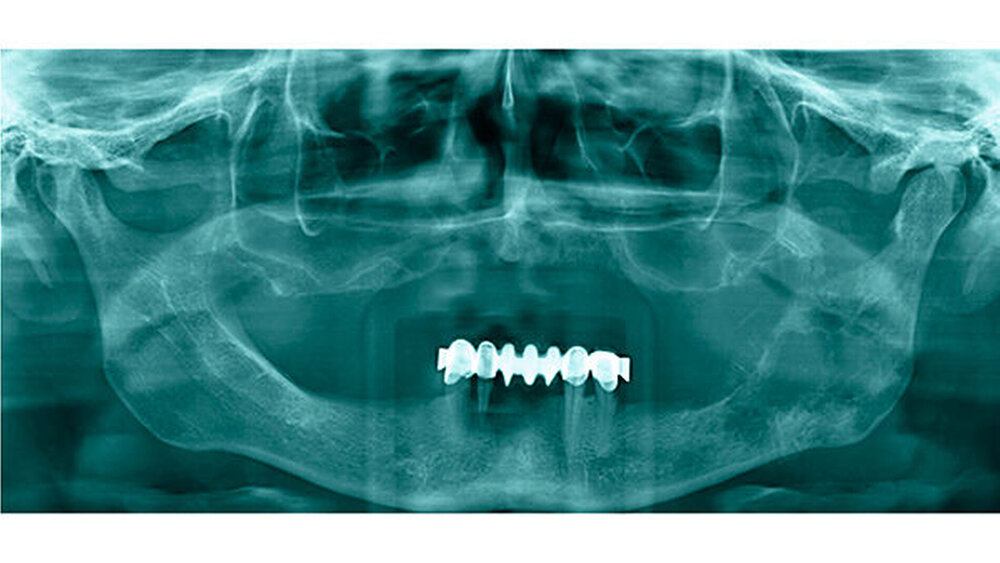

Klinisch präsentierte sich eine Auftreibung des Unterkiefers links mit Ulzeration im dritten Quadranten (Abbildung 2) bei einer auffälligen Anästhesie der linken Unterlippe. Tastbare Lymphknoten lagen nicht vor. In der Panoramaschichtaufnahme (Abbildung 3) zeigten sich linksseitig größtenteils osteolytische, partiell sklerotische Areale mit einem verplumpten Processus coronoideus. Hinweisgebend auf eine mögliche Diagnose waren schließlich die crestal gelegenen Spikulae. Eine alio loco bereits durchgeführte Probeexzision sicherte ein chondroblastisch differenziertes Sarkom.